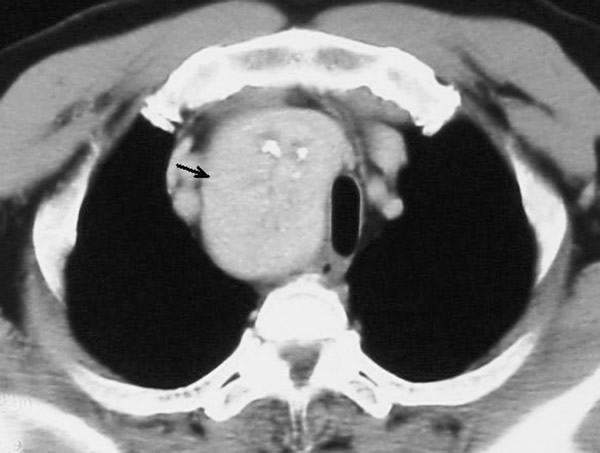

A 58-year-old Chinese man presented with a dry cough of three months’ duration. A chest x-ray at a local hospital revealed "a shadow in the superior mediastinum." A subsequent CT scan suggested "ectopic intrathoracic thyroid" (Figures 1 and 2). His physical examination revealed normal temperature and heart rate, without any signs of hyperthyroidism. Palpation of the neck revealed a non-tender, firm, fixed, and non-pulsatile 2 cm right inferior thyroid mass. A repeat chest x-ray confirmed a mass in the right anteromedial mediastinum, with smooth margins, tracheal compression, and deviation of the trachea to the left (Figure 3). Nuclear Tc99 thyroid scan revealed a cold nodule in the right inferior thyroid gland extending below the sternum (Figure 4). The values of total thyroxin 3 (TT3), total thyroxin 4 (TT4), free thyroxin 3 (FT3), free thyroxin 4 (FT4), and thyroid stimulating hormone (TSH) were all normal. Due to the suspicion of malignancy and to avoid the development of tracheomalacia, surgery was performed to remove the mass.

Figure 3: The arrow indicates the right upper mediastinal mass, trachea compressed. Figure 4: The arrow indicates the “cold” mass of right inferior thyroid that extends into the thorax.